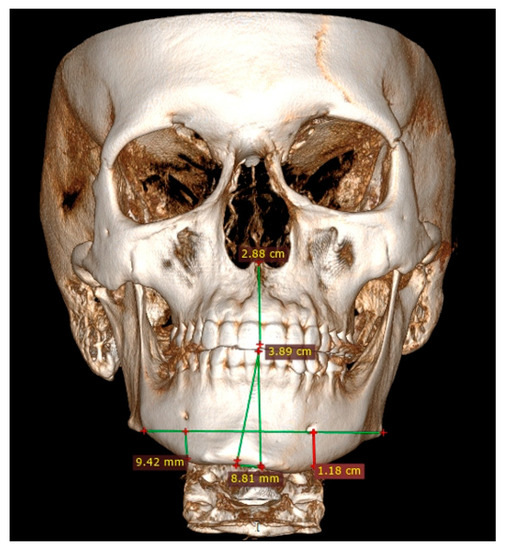

Figure 3.

LDCT—evaluation in low-dose CT focused on central symmetry line and differences in measurements between mental foramina, MIB, chin position, and mandibular angle contour.

Both panoramic radiographs and LDCT evaluations are important for any surgery planning. There is a possibility to estimate the shape and position of the mandibular canal while tracing its course on 3D evaluation and then estimating the degree of surgery in MIB (Figure 3 and Figure 4). Secondly, based on the studied patients’ data, the authors also include that the position of the mental foramina, chin deviation, and Go reference points described herein are valuable reference points for future surgical planning. Another important feature possible to estimate on 3D-LDCT is the scope of mandibular basis overgrowth in three dimensions.

At the first planning step, the authors proposed the investigation and measurement of the degree of bone overgrowth, using anatomical-topographical features consisting of known index measurements (IMs): the preoperative anatomical landmarks (Go-Go), (Go(Right)-Gn), (Go(Left)-Gn), and (Me–Gn) shown in Table 1. The used anatomical landmarks are commonly known [18,19,20,29,30,31,32,33]. Anthropometric points in this paper refer to ARP and consist of the following: gonion = Go refers to the most posteroinferior part of the mandibular angle; gnathion = Gn is located perpendicular on the mandibular symphysis midway between the pogonion and menton; menton = Me is the lowest point on the mandibular symphysis [20,21,22].

3.2. Gonial Angle

The length between Go-Gn/Go-Gn and the vertical bone volume relation decreases the bone height on the opposite healthy side—the critical point of this technique is the distance between the Go-Go/Go-Gn position and the value of the F0-C bone index. In this case, approach 1C can be used with or without corrective angulotomy/anguloplasty, which reduces the angled volume on the affected side in vertical and horizontal dimensions. If both Go (Right) and Go (Left) are situated on the same horizontal line, no major surgery should be planned, unless performing a condylectomy might relocate the Go point on the affected side to a higher position afterward. Therefore, careful planning in the horizontal plane and the F5: Go measurement can help estimate whether any additional mandibular angle surgery should be planned (Figure 1 and Figure 2; Table 1). This was used in some of the authors’ cases where there was no maxillary bite-plane deviation, and no chin bone asymmetry was present.

3.3. Chin Symmetry

The chin area position in IM and ARP (Figure 1)—severe chin area asymmetry—could be treated with the surgical approach suggested by Ferguson, while smaller ones could be successfully treated conservatively by drilling and bone reshaping or with other proposed methods of marginectomy. IM is used when the distance between C and F0 is equal (1:1); when C < F0 in both the vertical and horizontal dimensions, then a leveling and/or corrective genioplasty is used by the authors (Figure 1; Table 2). After the inferior dental neurovascular bundle is wholly free and retracted, bone correction and reshaping of the new inferior alveolar nerve canal is performed. Instead of a leveling genioplasty, the remnants of the overgrowth are smoothed with surgical drills. In the authors’ system, the primary key factor is total chin correction, which is necessary in cases of severe overgrowth; when F0 > C and Go-Gn>, there is >7 mm of vertical bone overgrowth, and the mandibular canal is positioned <5 mm from the MIB. The presented measurements are novel and not used in any previous reports and should be considered an additional tool for surgery planning.